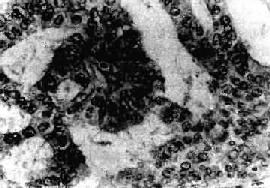

图13-9 子宫内膜腺

呈腺样结构,细胞呈柱状和立方形,核异型明显,排列紊乱